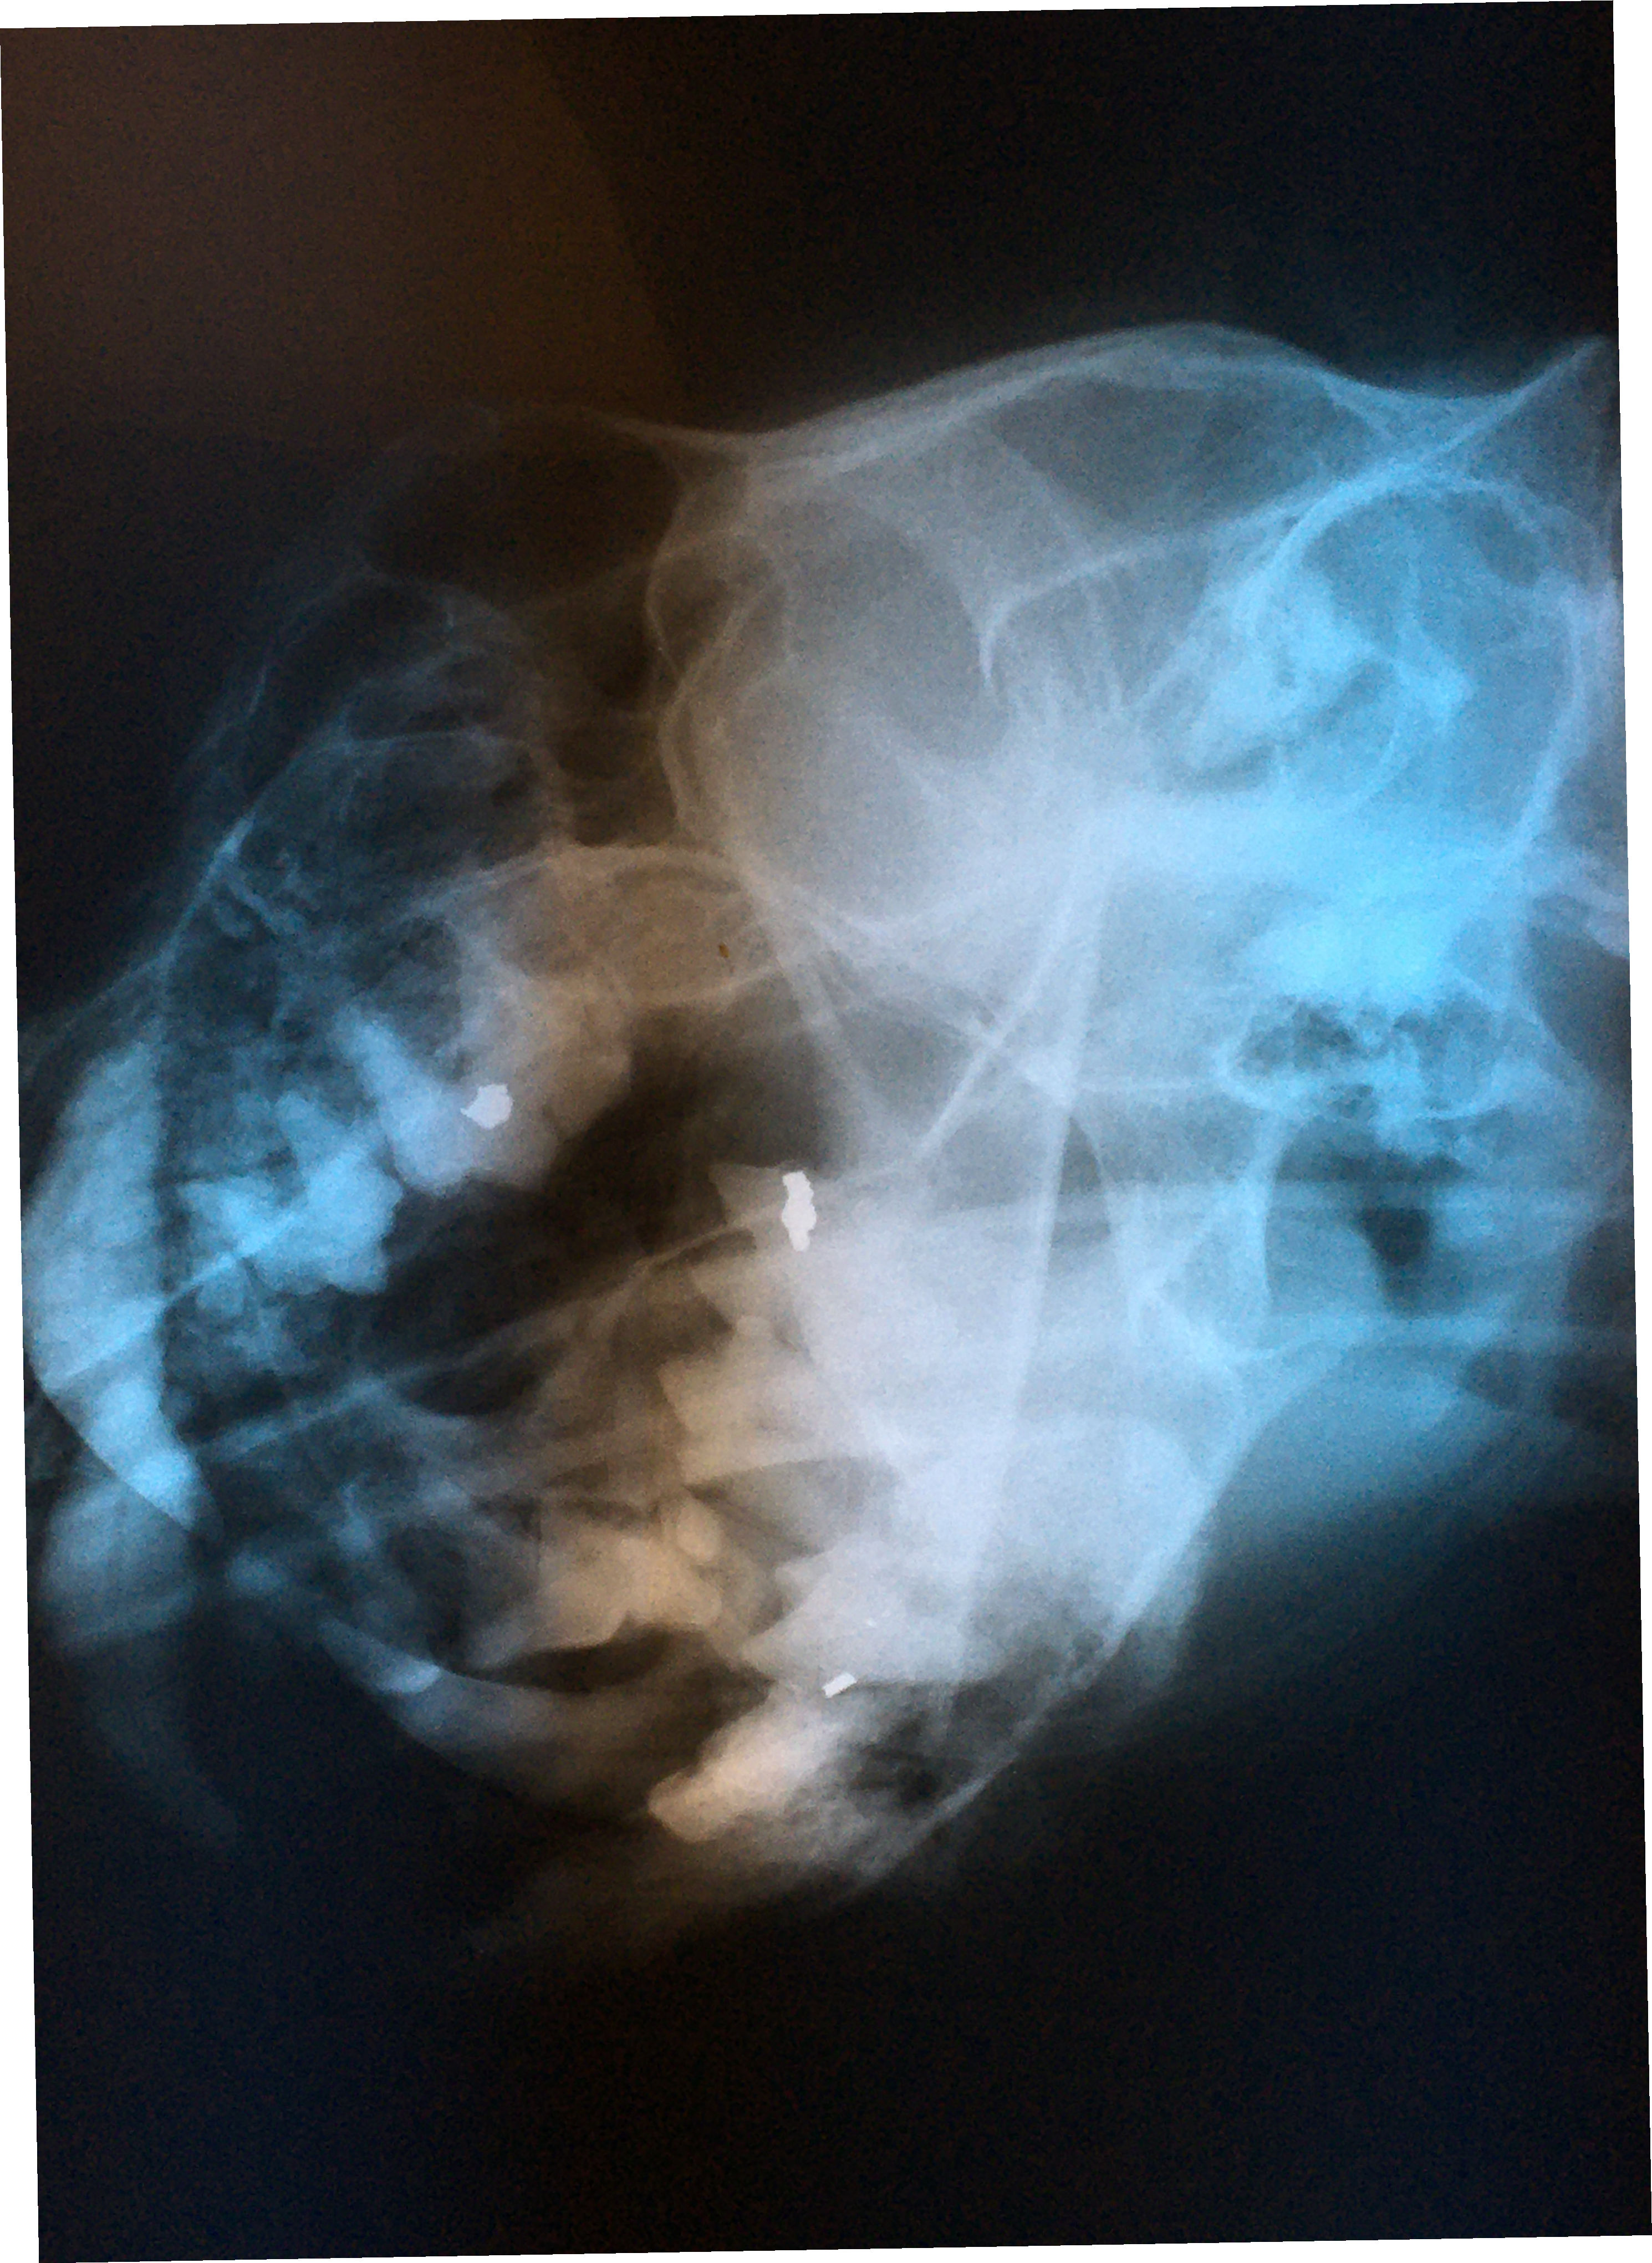

We learned to use the zoo hospital table radiography unit with fine grain and mammography film for full head views that are fully adequate for dental treatment. Right and left obliques are taken at 45 degrees with the mouth open. With proper positioning, each film will isolate one mandibular arch and one maxillary arch. Then with maxillary and mandibular dorsal-ventral intra orals, one will be provided with complete views of the entire arch.